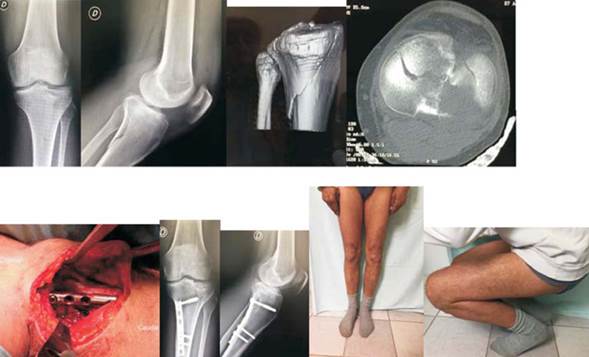

2. Paciente de 51 años. Sexo masculino. Accidente de moto. Las radiografías y tomografías muestran una lesión de tipo Schatzker II, sin luxación pero con compromiso AL, PL y central. El sector PL presenta un hundimiento grado 4 de De Coster, o sea mayor de 5 mm. Se realizó un abordaje PL y osteosíntesis con placa y tornillos. Resultado con función normal. Corresponde al caso Nº12 de la tabla 3 (figura 9).